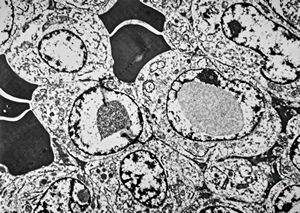

M,50y. | Pneumocystis carinii - lung